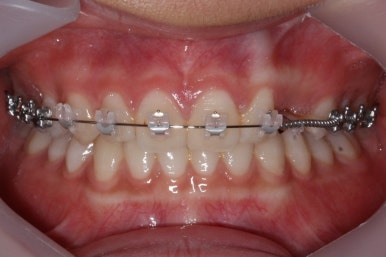

적절한 시기가 되면, 나머지 치아들을 가지런하게 할 준비를 합니다. 부산매복치아교정 키다리아저씨치과에서 이번에 사용한 장치는 클리피씨 입니다.

매번 말씀 드리지만 장치는 저마다 장단점이 있기 때문에 교정전문의와 잘 상의하여 선택하시면 됩니다.

이번 환자분의 경우는 아랫니는 약간 삐뚤함이 있지만 굳이 교정치료를 원하지 않으셨기 때문에 윗니들만 부분교정으로 해결하기로 했습니다.

이상적으로라면 위-아래를 한 쌍으로 해야 교합을 맞추기에 유리하지만 이번의 경우는 윗니만 해도 충분히 교합을 맞출 수 있겠다고 판단하여 부분교정을 하였습니다.

윗니만 하고 싶다고 무조건 윗니 부분교정이 가능한 것이 아니기 때문에 반드시 교정전문의와의 상의를 추천드립니다.